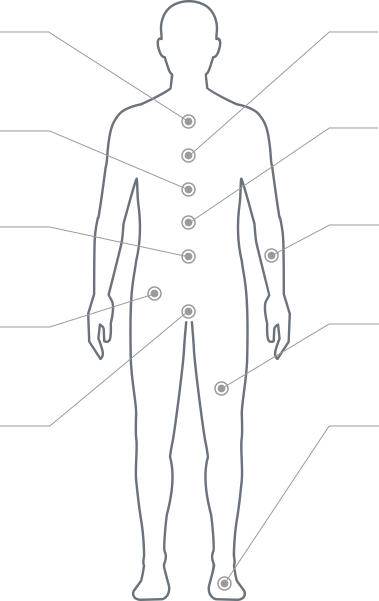

(Select all that apply)